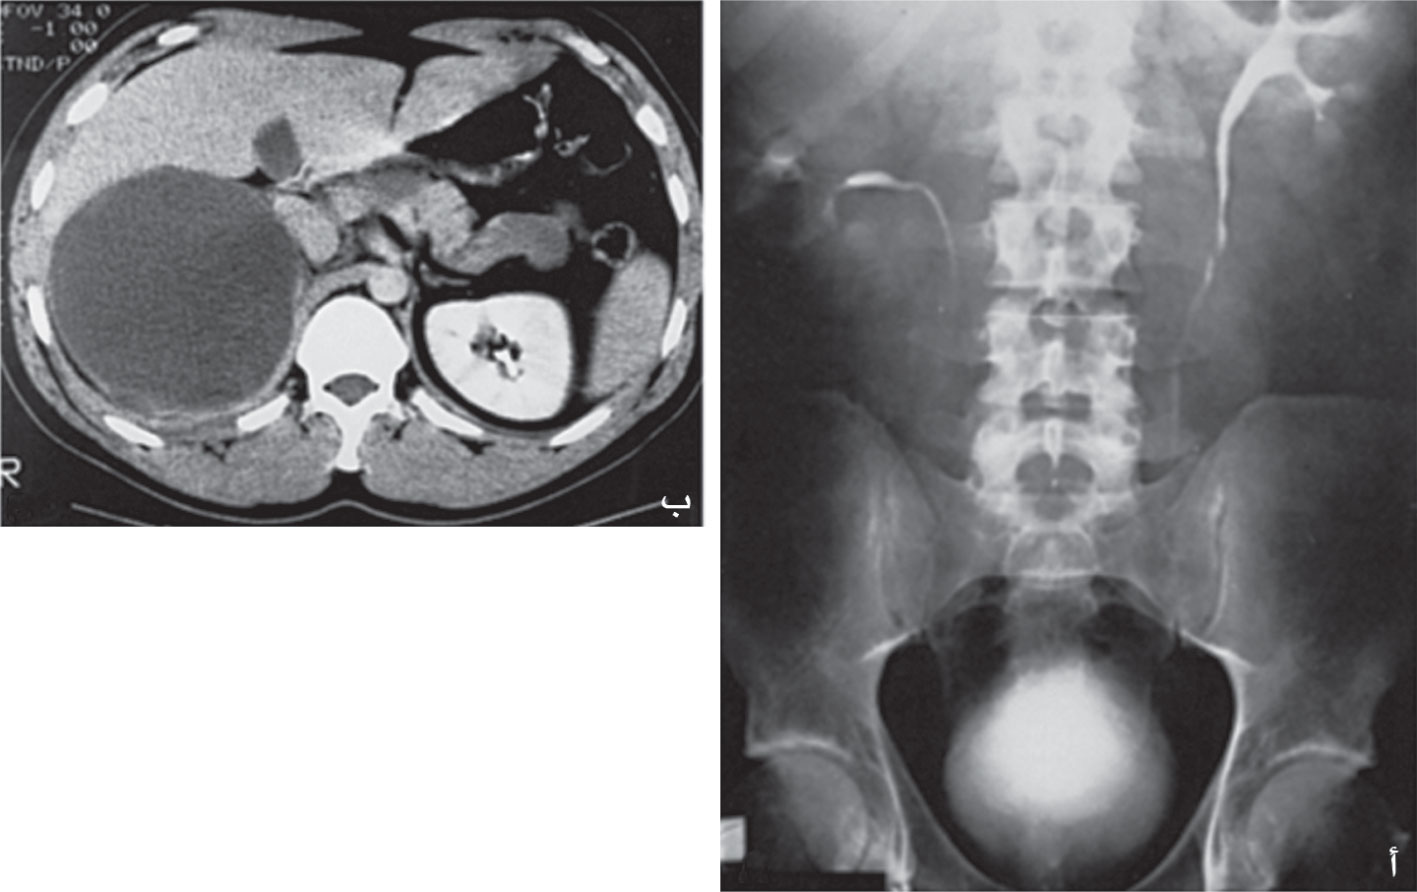

![]() |

الشكل (10) تصوير مقطعي محوسب يظهر سرطانة الكظر. |

التشخيص الشعاعي: يعتمد على التصوير المقطعي المحوسب CT والتصوير بالمرنان MRI (الشكل 10). تظهر المقاطع المعترضة انزياح الكلية إلى الأسفل وتغير محورها في الجهة نفسها؛ ولكن هذه التغيرات لا تظهر إلا إذا كان طول الكتلة أكبر من 2-3سم.